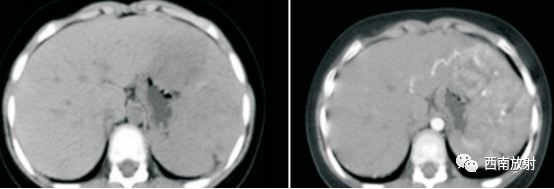

1、CT表现:平扫期可见肝实质性肿块,边缘清楚或不清,内可见多发散在更低密度区,肿瘤常突入腹腔,内可见钙化灶;增强期可见多个结节状增强染色征象,病灶周围呈结节状、片状明显强化,密度高于肝脏,门脉期呈低密度。

▲病例6:男,1岁,肝左右叶肝母细胞瘤,化疗前CT平扫肝内见一巨大稍低密度肿块影,密度不均匀,内见不规则斑片状更低密度影及沙粒 状钙化灶分布(长箭头 ),病灶边界模糊。穿刺活检为混合型肝母细胞瘤。化疗后,肿瘤 体 积 明 显 缩小(短箭头),其内钙化增多(长箭头 )。

(病例4-6来源:李宝兰 .张 毅.肝母细胞瘤的 CT表现与病理对照 (附 11例报告 )[J].牡丹江医学院学报,2007,28(2):58-60.)